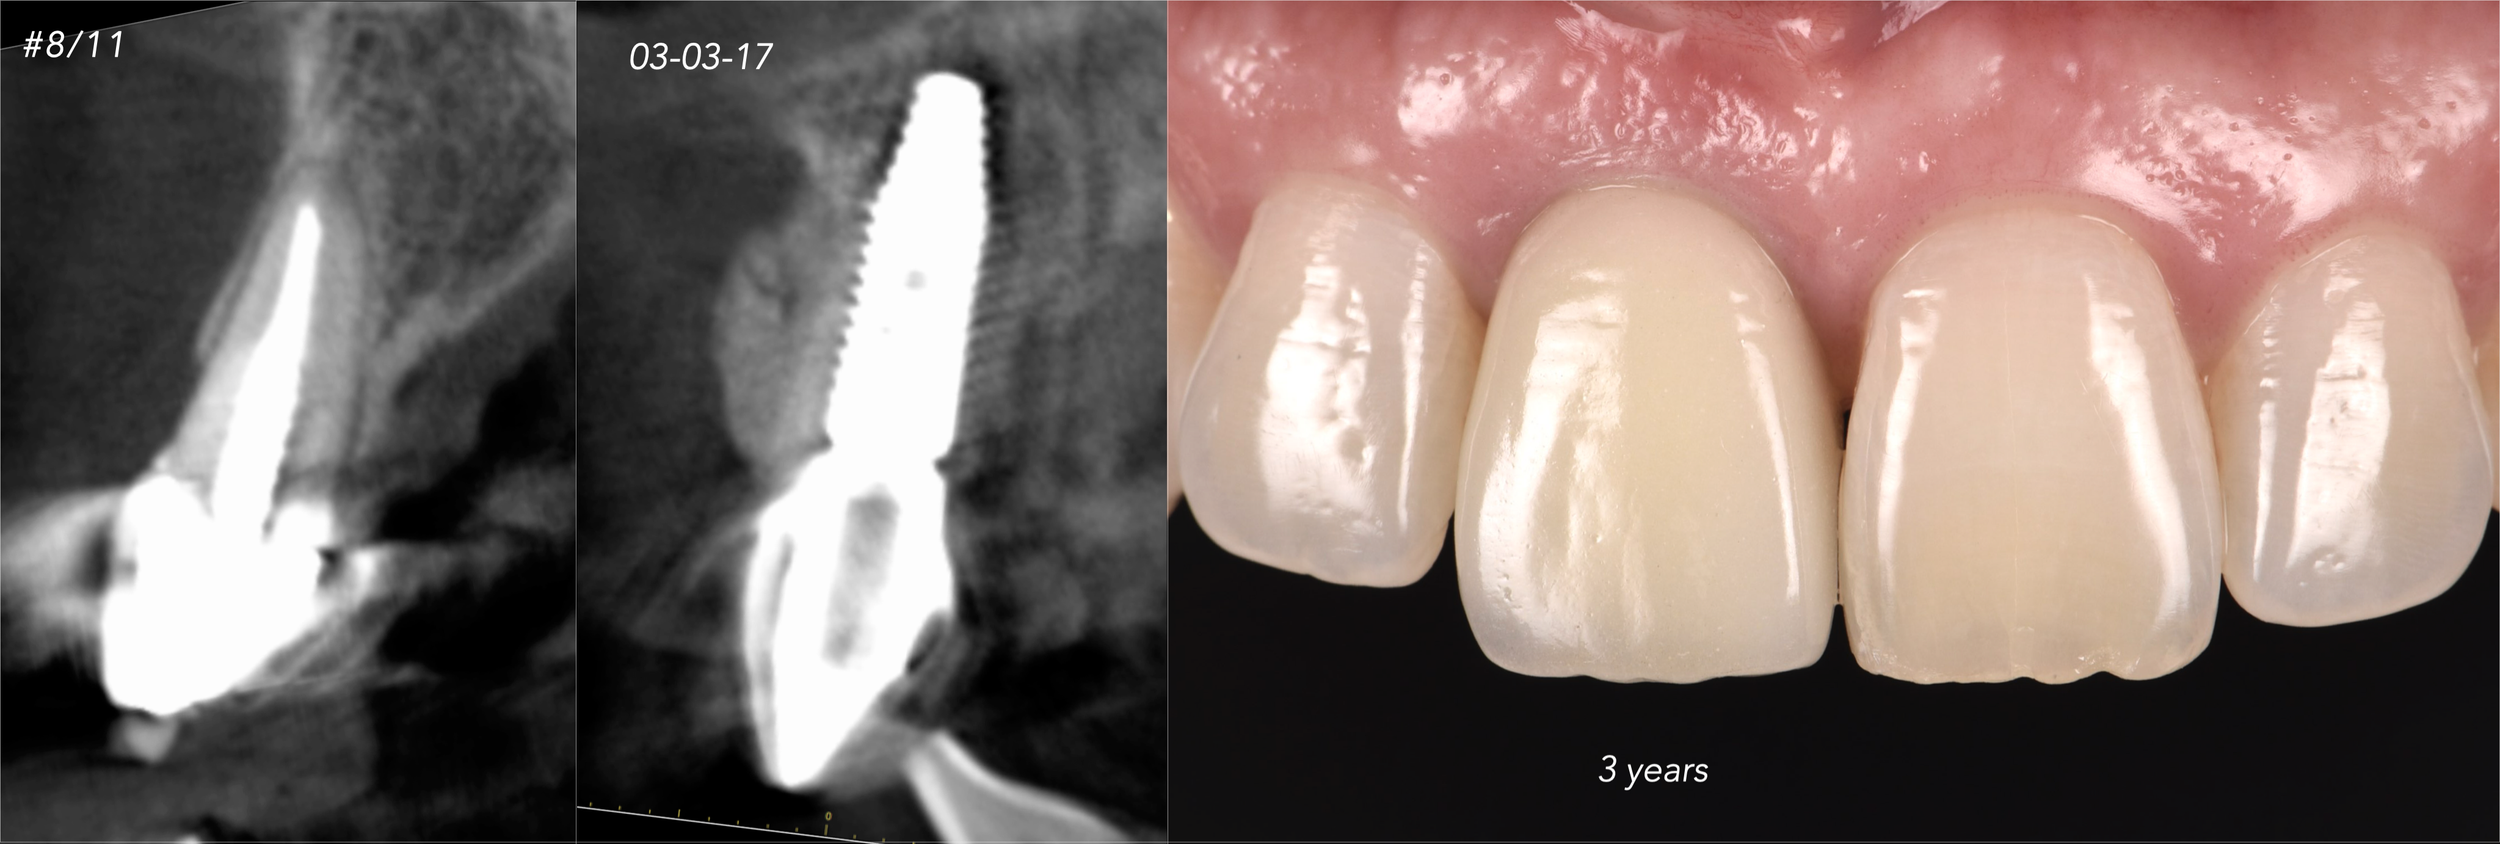

CASE 8. IMMEDIATE IMPLANT AND SIMULTANEOUS S.M.A.R.T.® HORIZONTAL AUGMENTATION